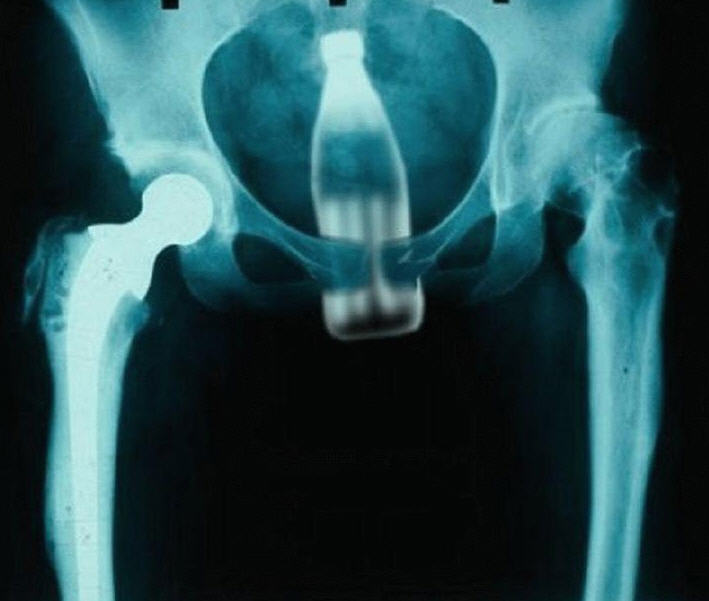

X - rays, taking photograhpy a step further

Attached Thumbnails

Click image for larger version

Name:	787-nice-xray.jpg

Views:	94

Size:	42.1

ID:	10578